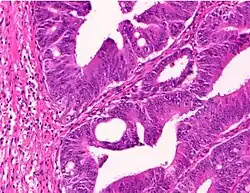

Adenocarcinoma is a malignant epithelial tumor, originating from superficial glandular epithelial cells lining the colon and rectum. It invades the wall, infiltrating the muscularis mucosae layer, the submucosa, and then the muscularis propria. Tumor cells describe irregular tubular structures, harboring pluristratification, multiple lumens, reduced stroma ("back to back" aspect). Sometimes, tumor cells are discohesive and secrete mucus, which invades the interstitium producing large pools of mucus. This occurs in mucinous adenocarcinoma, in which cells are poorly differentiated. If the mucus remains inside the tumor cell, it pushes the nucleus at the periphery, this occurs in "signet-ring cell." Depending on glandular architecture, cellular pleomorphism, and mucosecretion of the predominant pattern, adenocarcinoma may present three degrees of differentiation: well, moderately, and poorly differentiated.[5]

Cancer – Invasive adenocarcinoma (the most common type of colorectal cancer). The cancerous cells are seen in the center and at the bottom right of the image (blue). Near normal colon-lining cells are seen at the top right of the image. -

- Invasive adenocarcinoma commonly displays:[6]

- Varying degrees of gland formation with tall columnar cells

- Frequently desmoplasia

- Dirty necrosis, consisting of extensive central necrosis with granular eosinophilic karyorrhectic cell detritus.[6][7] It is located within the glandular lumina,[7] or often with a garland of cribriform glands in their vicinity.[6]